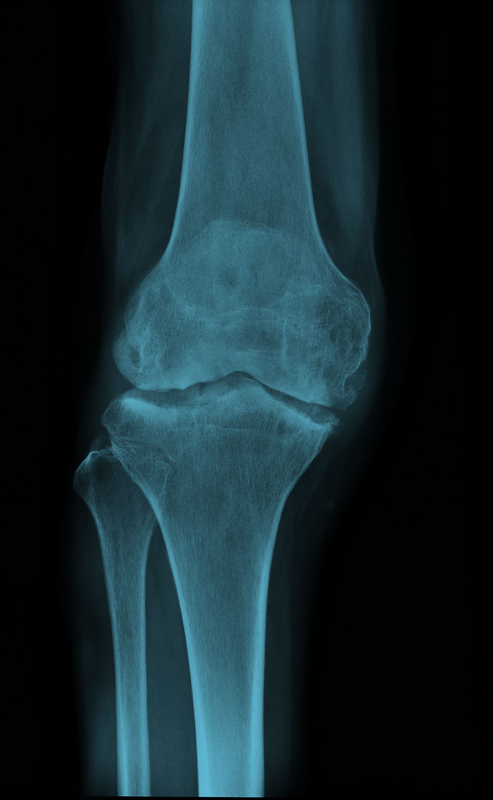

РОЗПІЗНАЙТЕ НА РЕНТГЕНОГРАМІ СУГЛОБ, ЩО СКЛАДАЄТЬСЯ З ТРЬОХ СУГЛОБІВ, ЯКІ МАЮТЬ СПІЛЬНУ КАПСУЛУ.

СУГЛОБ СКЛАДНИЙ. СУГЛОБОВА КАПСУЛА ТОНКА, УТВОРЮЄ БАГАТО СУМОК, ЯКІ СПОЛУЧАЮТЬСЯ ІЗ СУГЛОБОВОЮ ПОРОЖНИНОЮ. ЦЕ СПРИЯЄ ПЕРЕХОДУ ЗАПАЛЬНИХ ПРОЦЕСІВ (Є ДІАГНОЗ: БУРСИТ). ДЕ ВИ БАЧИТЕ ЦЕЙ СУГЛОБ.

РОЗПІЗНАЙТЕ СКЛАДНИЙ СУГЛОБ, ЯКИЙ СКЛАДАЄТЬСЯ З ТРЬОХ КІСТОК, ОДНА З ЯКИХ РОЗТАШОВАНА В СУХОЖИЛКУ ЧОТИРИГОЛОВОГО М'ЯЗА СТЕГНА.

СУГЛОБ СКЛАДНИЙ. УТВОРЕНИЙ СУГЛОБОВИМИ ПОВЕРХНЯМИ МЕДІАЛЬНОГО І ЛАТЕРАЛЬНОГО ВИРОСТКІВ, ЯКІ Є В ОБОХ КІСТКАХ, ЩО ЙОГО УТВОРЮЮТЬ. РОЗПІЗНАЙТЕ СУГЛОБ.

Запитання 61